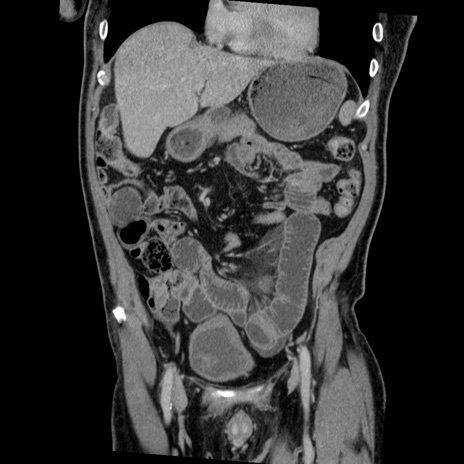

症例22(冠状断像)

【症例】50歳代男性

【主訴】腹痛

【現病歴】AVMからの被殻出血のため回復期リハ病棟入院中。 本日午後3時頃急に下腹部痛が出現した。

【既往歴】AVM、被殻出血、虫垂炎、高血圧

【身体所見】意識晴明、左半身不全麻痺、会話の理解は良好、36.5°C、腹部:膨隆、全体に板状硬、下腹部正中に圧痛点あり、反跳痛-、筋性防御不明、右下腹部にope scar

【データ】WBC 9400、CRP 0.06